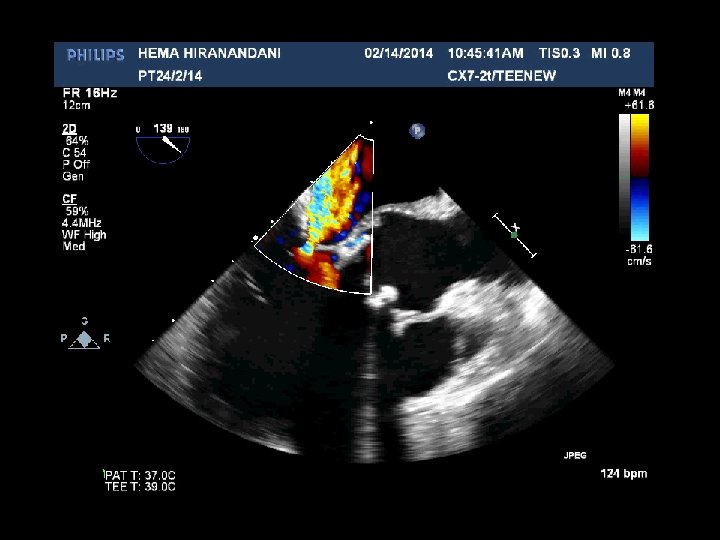

HEMA HIRANANDANI F 57 YRS • • • AVR BIO PROSTHETIC VALVE DEHISCENCE IE MULTIPLE VEGETATIONS ON BIO PRO VALVE AO ROOT ABSCESS SEVERE PARAVALVULAR AR RVSP= 37 mmhg

Hema Hirandani